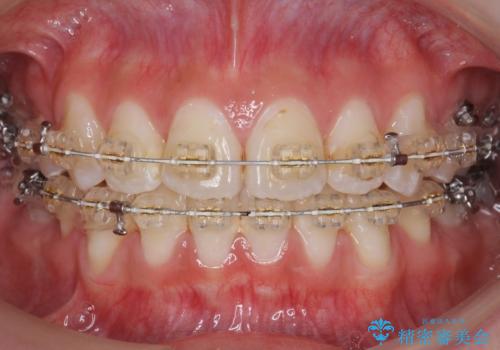

八重歯の治療 仕上がり重視で

- 八重歯を主訴に来院。

仕上がり重視とのことで、小臼歯を抜歯し、スタンダードな治療方法で仕上げています。

上下の小臼歯を抜歯しています。

矯正用インプラントアンカーを使用してしっかり前歯を下げたため、口元が大きく改善しています。